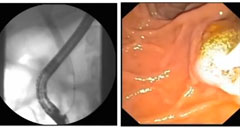

Extracción de cálculos complicados de las vías biliares con el sistema de visualización directa SpyGlass®

En este video se explica la técnica de extracción guiada por colangioscopía de cálculos complicados de las vías biliares.